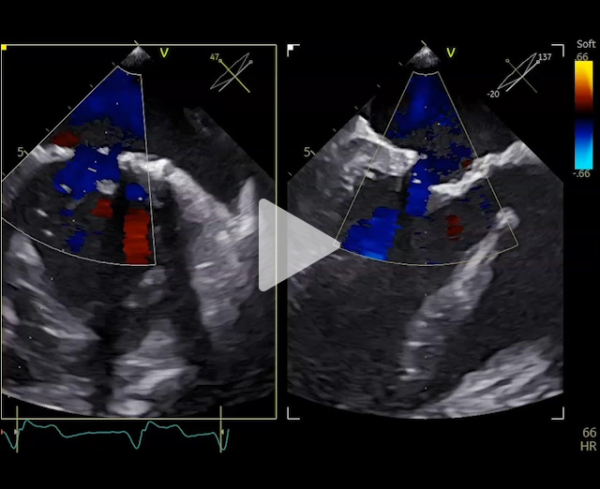

Nouvelle évaluation globale : ETT - ETO

Vidéo 3

- Ventricule gauche dilaté 87 ml/m2, FEVG 79%.

- Oreillette gauche dilatée 55 ml/m2

- Valve mitrale : plastie mitrale sur valve barloïde, insuffisance mitrale de grade 3

- Restriction au niveau de P3

- SOR 30 mm2, VR 54 ml, PISA 8 mm

- Rapport ITV 1,8, onde E 1,8 m/s

- Pas de reflux dans les VP

- Gmoy 6 mmHg

- Fonction ventriculaire droite altérée

- Forte probabilité d’HTP